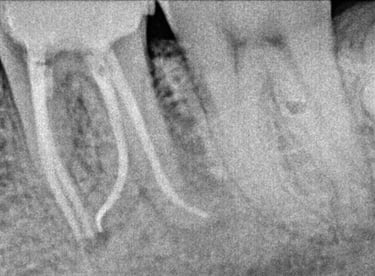

Root Canal Treatment near Shyamal, Ahmedabad

Before

After

All images shown here represent real clinical cases treated at our dental clinic with patient consent.

At Shree Dental Care, we focus on gentle, precise, and well-planned root canal treatment to remove infection, relieve pain, and preserve your natural tooth structure.

Patients from Shyamal and nearby areas of Ahmedabad visit our clinic for comfortable root canal procedures carried out using modern techniques and strict hygiene protocols. The treatment helps eliminate infection from inside the tooth, prevents further damage, and restores normal chewing function.